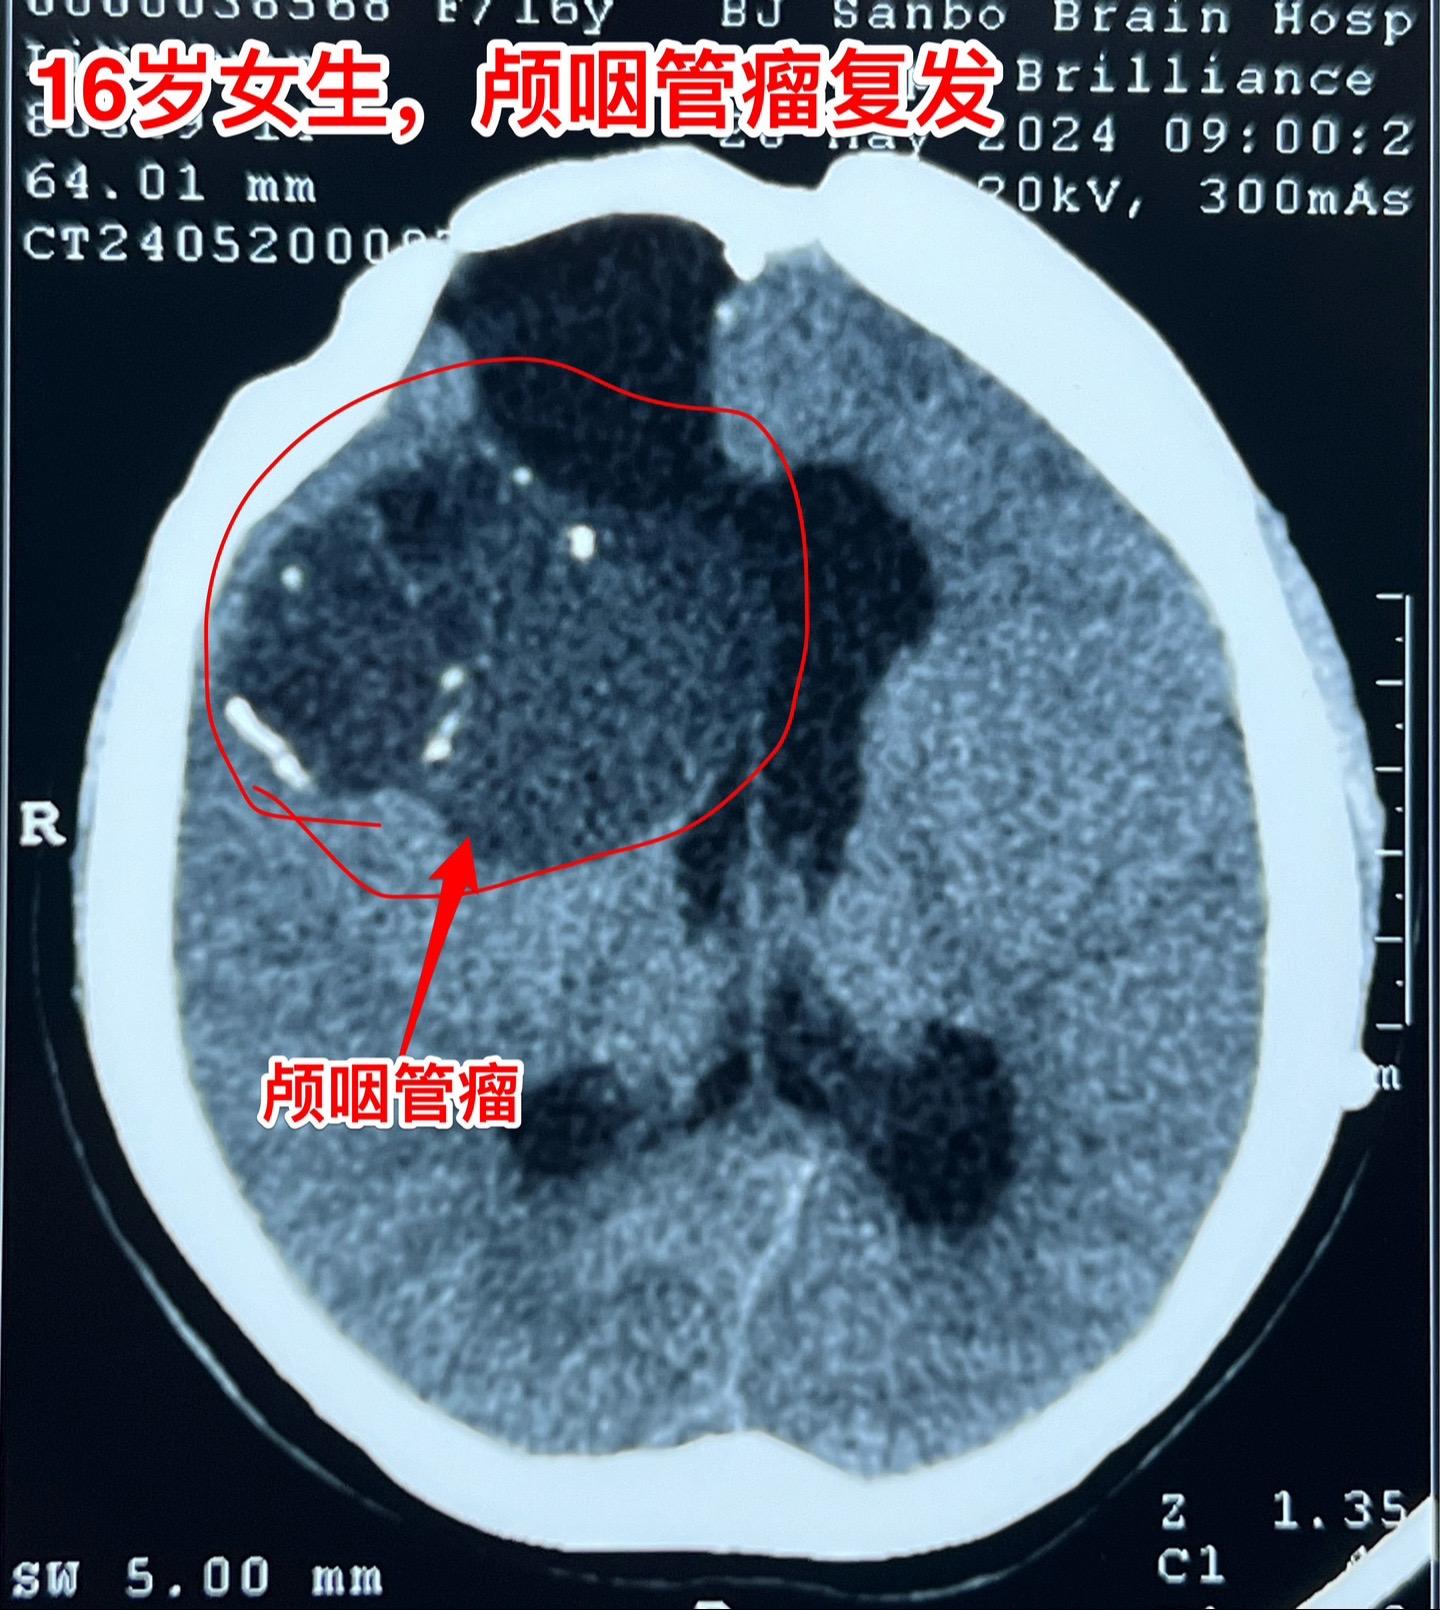

16岁女生颅咽管瘤第三次手术。第二次手术是在2013年1月。那次手术后还因脑积水作了脑室腹腔分流术。出院后能上学读书,而且内分泌方面还不错。有点遗憾的是额部手术疤痕及颅骨变形影响了病人的容貌。 这次的手术原计划在5月28日进行,因为她的生理周期突然提前了(自然的周期)故而将手术推迟到6月4日进行。肿瘤得到完全切除。 这次的肿瘤体积很大,但是还没有影响到垂体-下丘脑,可以预见,她的内分泌功能不会受到破坏。只希望她的肿瘤不再复发。内分泌

16岁女生颅咽管瘤第三次手术。第二次手术是在2013年1月。那次手术后还因脑积水作了脑室腹腔分流术。出院后能上学读书,而且内分泌方面还不错。有点遗憾的是额部手术疤痕及颅骨变形影响了病人的容貌。 这次的手术原计划在5月28日进行,因为她的生理周期突然提前了(自然的周期)故而将手术推迟到6月4日进行。肿瘤得到完全切除。 这次的肿瘤体积很大,但是还没有影响到垂体-下丘脑,可以预见,她的内分泌功能不会受到破坏。只希望她的肿瘤不再复发。颅咽管瘤内分泌